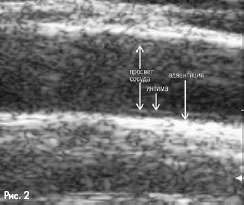

Измерение ТИМ

ТИМ измеряется по методике P.Pignoli как расстояние между характерной эхо-зоной, образованной поверхностями просвет-интима и медия-адвентиция в поперечном сечении вручную при помощи электронного штангенциркуля. На рис.2 продемонстрированы границы интимы-медии-адвентиции.

Угол ультразвукового сканирования перпендикулярен к оси сосуда. Диаметр сосуда измеряется в систолу и диастолу как расстояние между наиболее удаленными точками внутренней поверхности сосуда (граница просвет-интима) в поперечном сечении вручную при помощи электронного штангенциркуля или автоматически с использованием специального программного обеспечения. Границы просвета сосуда продемонстрированы на рис. 2.